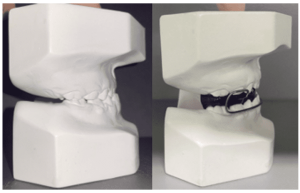

A 49-year-old female patient attended the prosthesis clinic at Nilton Lins University, mentioning dissatisfaction with her total obturator prosthesis, because she had a “broken front tooth” and the prosthesis was “falling”, emphasizing the desire to maintain the shape of the same. In the anamnesis reported that previously in 2012 he was diagnosed with mucoepidermoid carcinoma of intermediate degree in the palate (Appendix 1) and in 2013 after performing surgical removal and performing new tests, who did not indicate the presence of malignancy (Appendix 2), was attested as cured, besides being hypertensive and using the drugs losartan potassium 50 mg twice daily and levanlodipine besidate 2.5 mg once a day. No alterations were observed on extraoral clinical examination. In the intraoral clinical examination, there was absence of the upper arch teeth, bucosinusal communication and partial maxillary edge and in the lower region only the presence of teeth 31, 32, 33, 41, 42, 43, 44 and 45 (figures 1 and 2).

Figure 2: Initial aspect of the patient in occlusion.

After acrilization of the obturator prosthesis, it was installed in order to verify the necessary adjustments still with the PPR test base, with no need for adjustments (figure 20). The PPR was sent for acrylization and at the end the prostheses were installed checking the adjustments again, verifying favorable adaptation, reestablishing comfort, function and aesthetics for the patient (figure 21).

Figure 21: Final aspect.